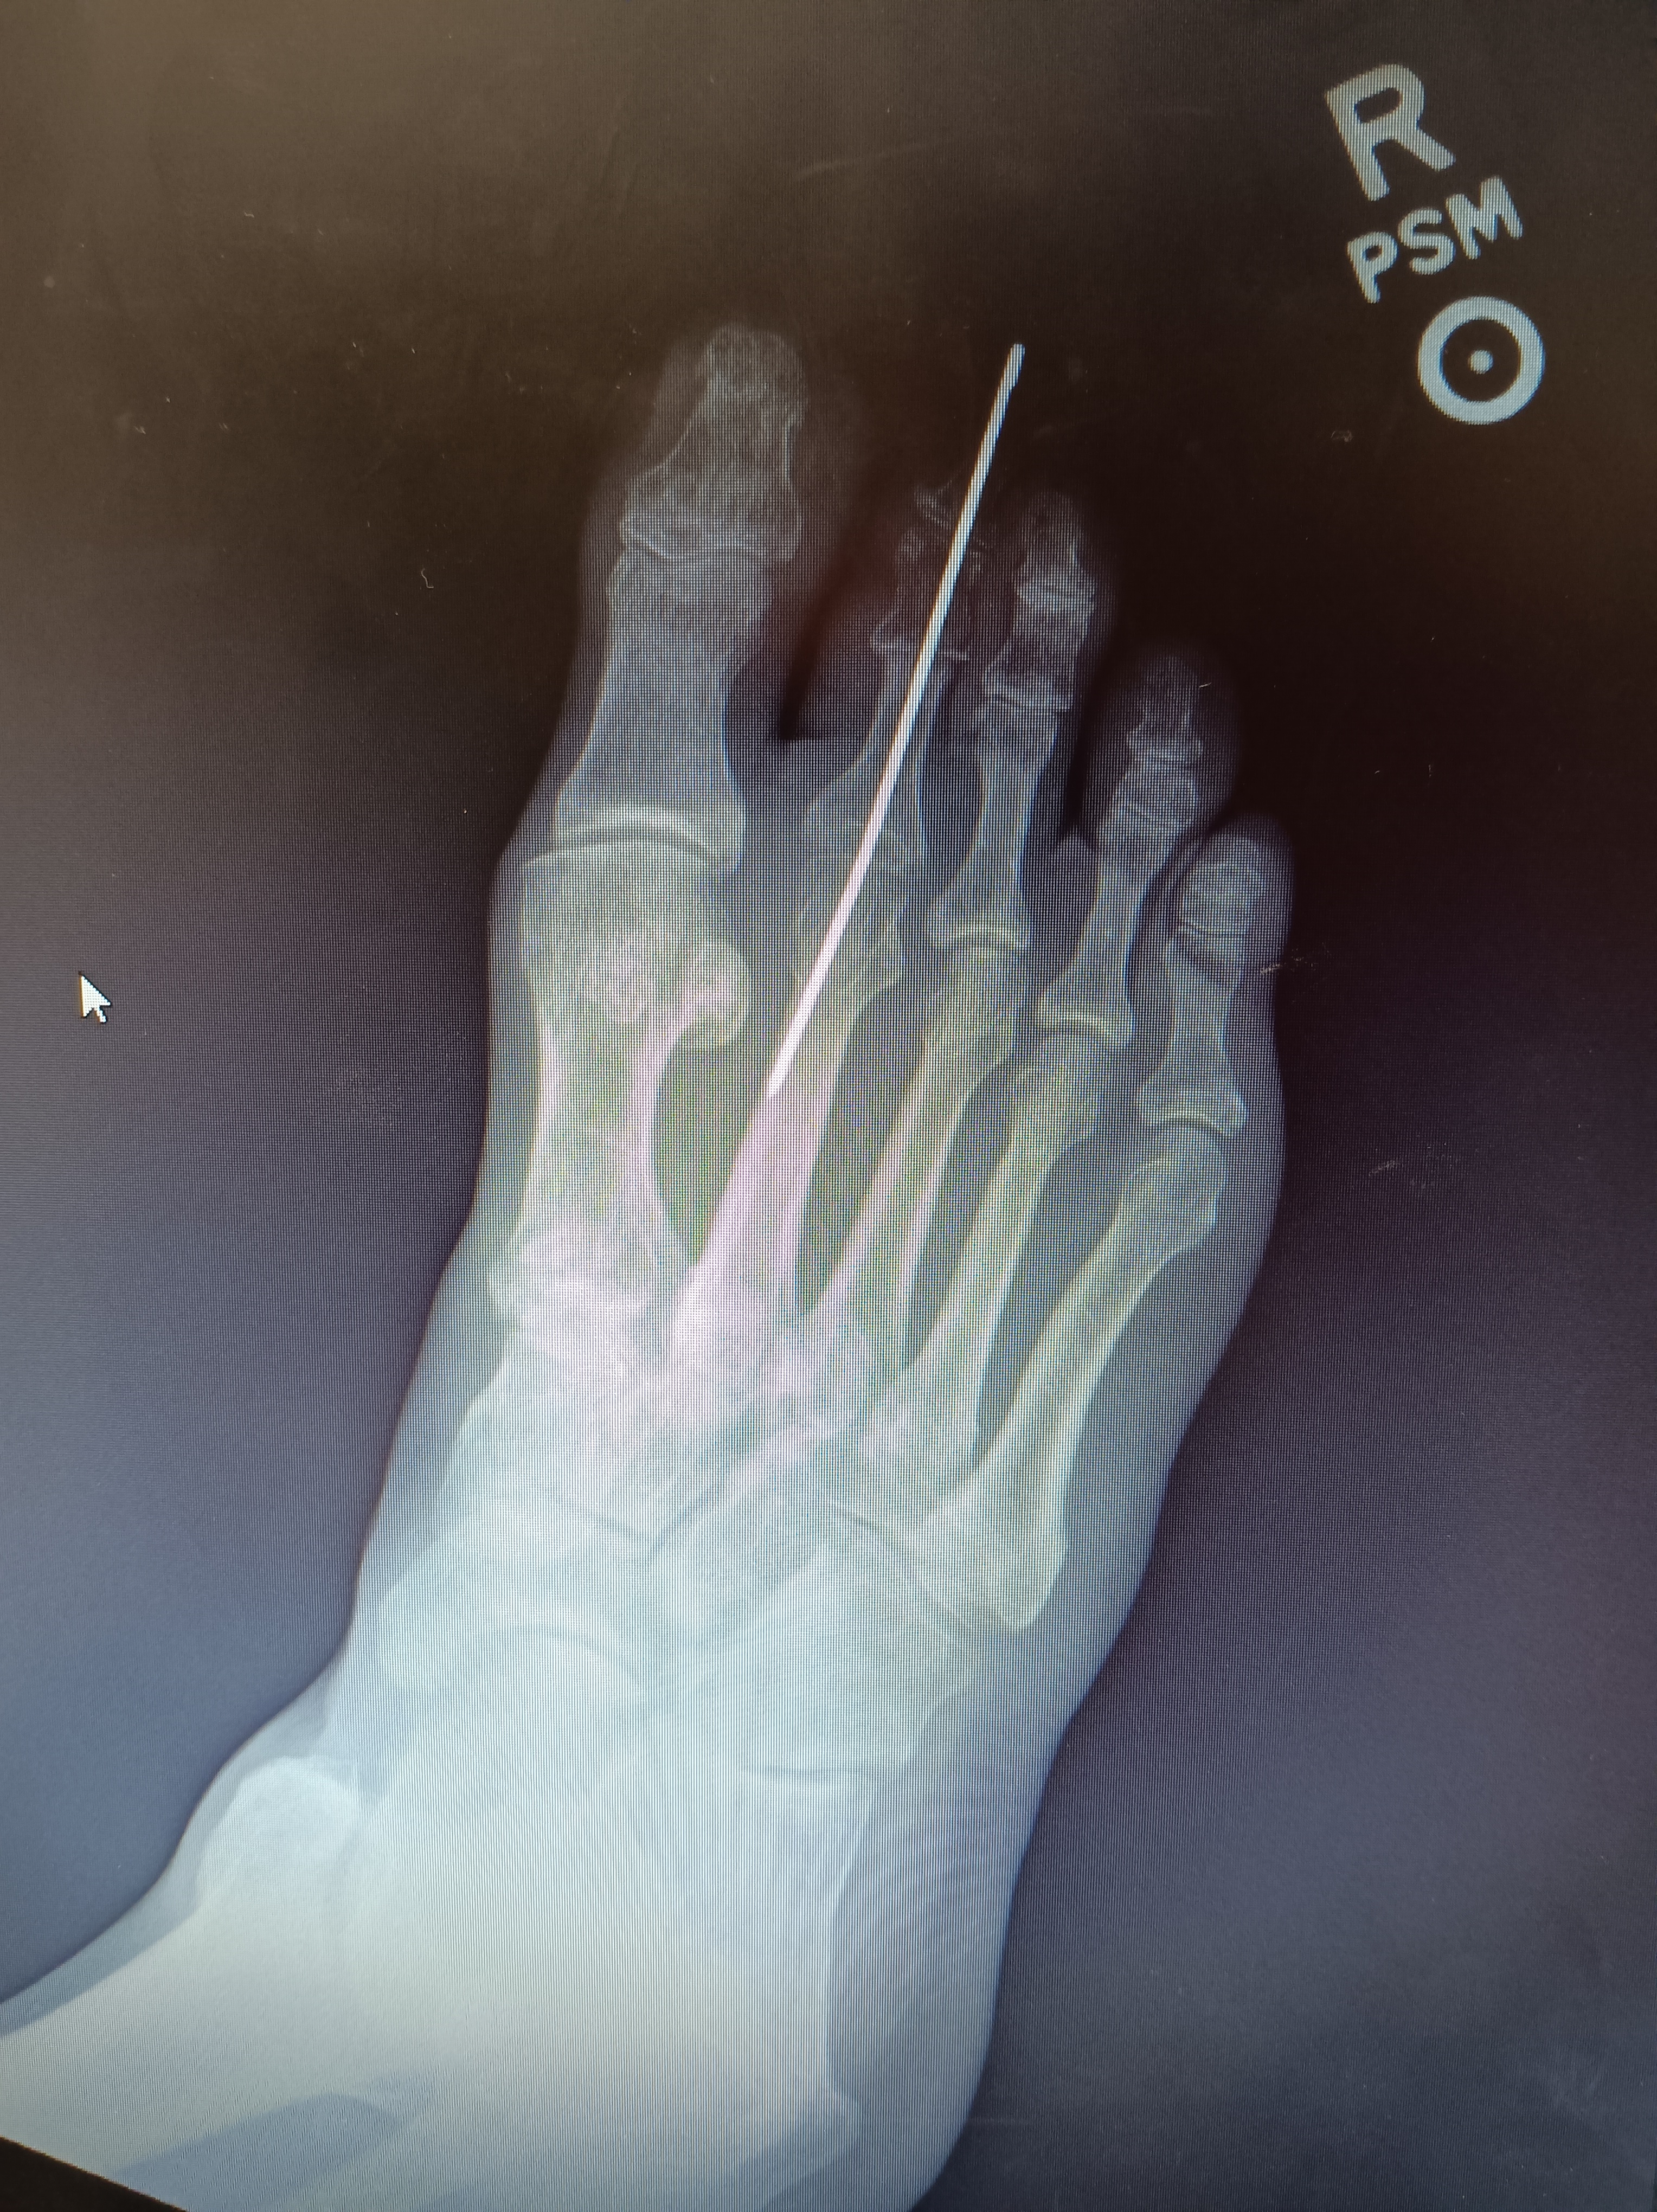

For about a year I’ve been developing another hammer-toe on the next-to-largest toe of my right foot. Hammer-toe is a disorder of the toe joints causing the joint to knuckle up in a close to 90-degree bend, causing pain when walking.

From Wikipedia: ‘a deformity of the proximal interphalangeal joint of the second, third, or fourth toe causing it to be permanently bent, resembling a hammer’

‘Hammer toe’ is a joint dislocation that can only be corrected, in its ‘frozen’ state, by surgery of the affected toes, ligaments and muscles. The surgeon removes bone so the toes can lie flat again and pins are inserted to make them heal that way. The pins will be removed later.’

On Halloween my sister took me in for x-rays and pin removal- thanks sis! Surprisingly, the doctor uses a common pair of slip-joint pliers to quickly twist and jerk out the pin with virtually no pain. That was a happy day since it’s deeply weird to clump around with a steel pin in the toe.